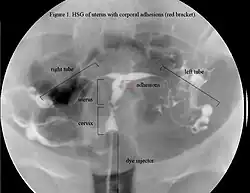

El predominio verdadero del SA está confuso así como muchos doctores desconocen los síntomas o el diagnóstico. Se estima que hasta el 5% de las D&C causan el SA [cita requerida]. Estimaciones más conservadoras pusieron este índice en el 1% [cita requerida], sin embargo, esto parece ser desestimado dado la incidencia de las adherencias intrauterinas siguiendo el curetaje reportado en estudios prospectivos y la cantidad de dilataciones y curetajes realizados anualmente. El aumento de la concienciacion de la condición y su diagnóstico también esperó revelar una frecuencia más alta que la divulgada previamente. La condición fue encontrada en 1,5% de las mujeres que demostraron HSG, 18 y entre 5 y el 39% de mujeres con abortos involuntarios repetitivos. 19 20 21.

La historia del acontecimiento del embarazo seguido por la dilatación y el legrado liderizado por la amenorrea secundaria o a la hipomenorrea es común. La histeroscopia es el estándar de oro para el diagnóstico. 3 La proyección de sonohisterografía o histerosalpingografía podría revelar el grado de la formación de la cicatriz. El ultrasonido no es un método confiable de diagnosticar el Síndrome de Asherman. Los estudios de la hormona muestran los niveles normales constantes con la función reproductiva.